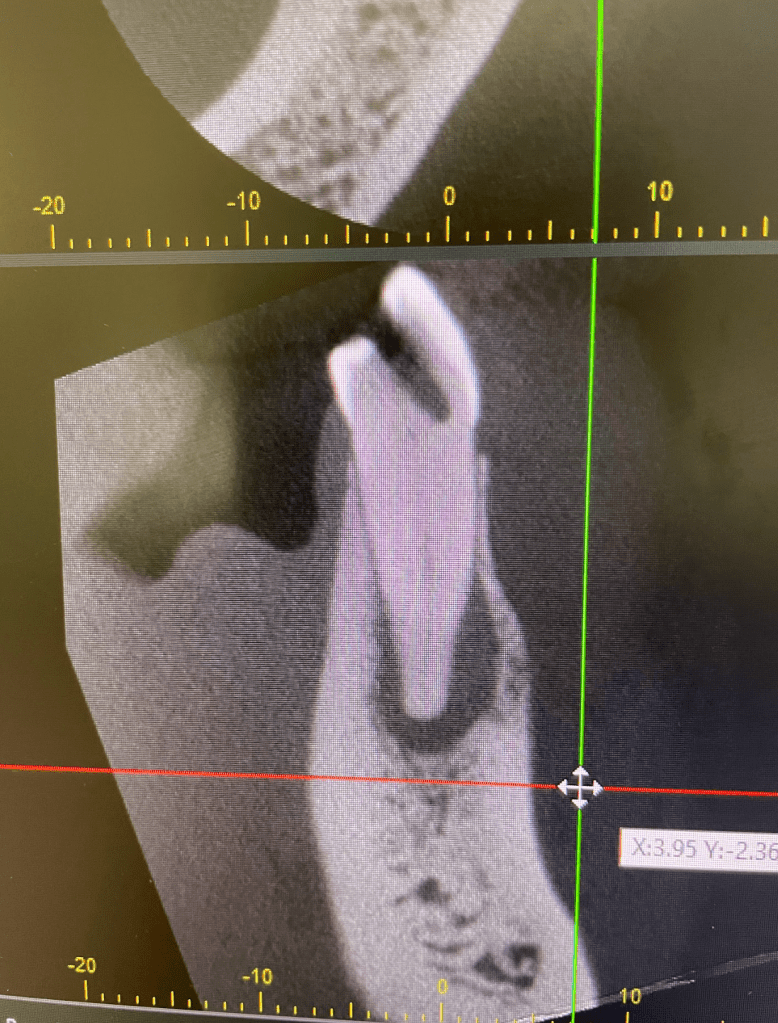

CALCIFICADOS

Premolar calcificado lesion